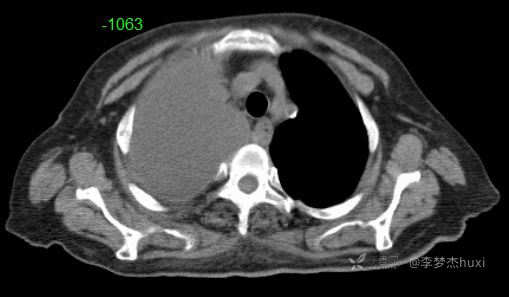

女性78岁,右侧满罐胸水,你绞尽脑汁也想不到的原因

主诉:主因胸闷伴腰背部疼痛1个月

简要病史:患者缘于入院前1个月无明显诱因出现胸闷不适,进行性加重,无明显咳嗽、咳痰,无胸痛及咯血,无喘息,伴进食差,食欲明显减退,无恶心、呕吐,无腹痛、腹泻,伴腰背部疼痛,活动后明显,无尿便失禁,无发热,院外未治疗,来诊

临床诊断:右侧胸腔积液